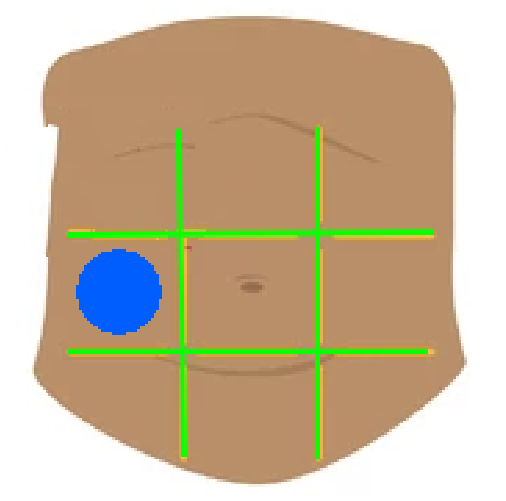

Right hypochondriac region

Left hypochondriac region

Epigastric region

Right lumbar region

Left lumbar region

Umbilical region

Right inguinal region

Left inguinal region

Hypogastric regions